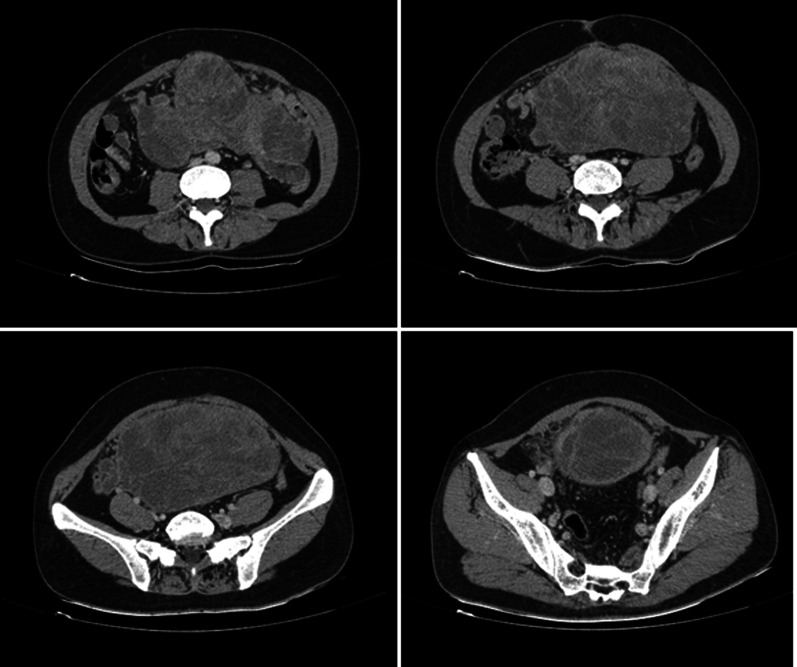

A contrast-enhanced computed tomography (CT) (Fig. 1) was performed which showed a large heterodyne, multilobulated lesion sized 20 × 15 × 10 cm occupying the entire pelvis and extending up to the supra-umbilical region.

Fig. 1.

Axial contrast-enhanced computed tomography (CT) of a primary intra-abdominal synovial sarcoma in a 40-year-old woman. A large heterodense, multilobulated lesion with a size of 20 × 15 × 10 cm

The right ureter and kidney were closely abutting the lesion, but there was no evidence of locoregional invasion into the adjacent viscera. There was no vascular invasion. Despite all these findings, the lesion was deemed resectable.